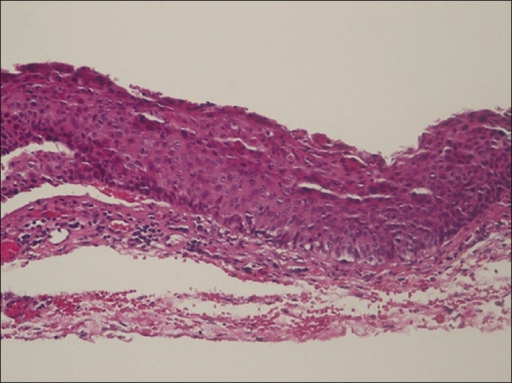

- 상방 구결막 충혈/비후

- 상방 윤부/각막: rose bengal/lissamine green 양성 염색

- 상안검 결막: 유두 반응